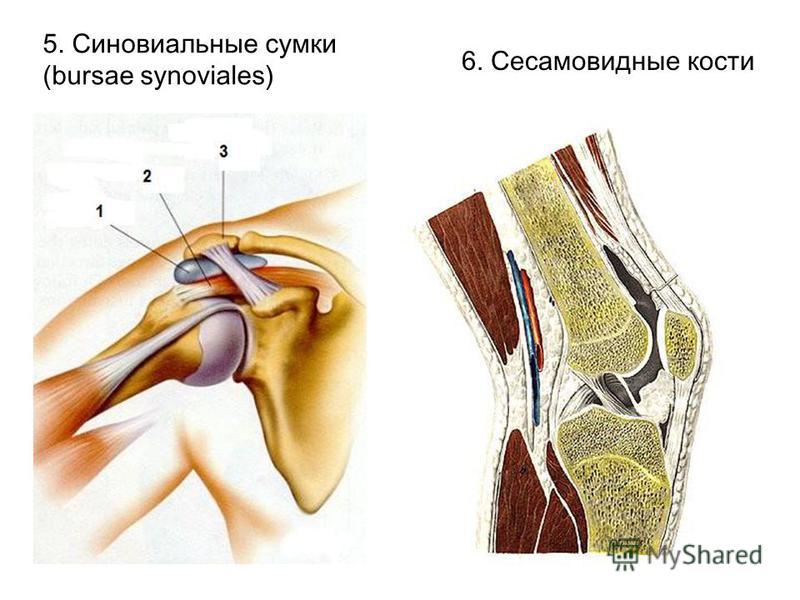

Анатомия: Блоки и сесамовидные кости в деталях